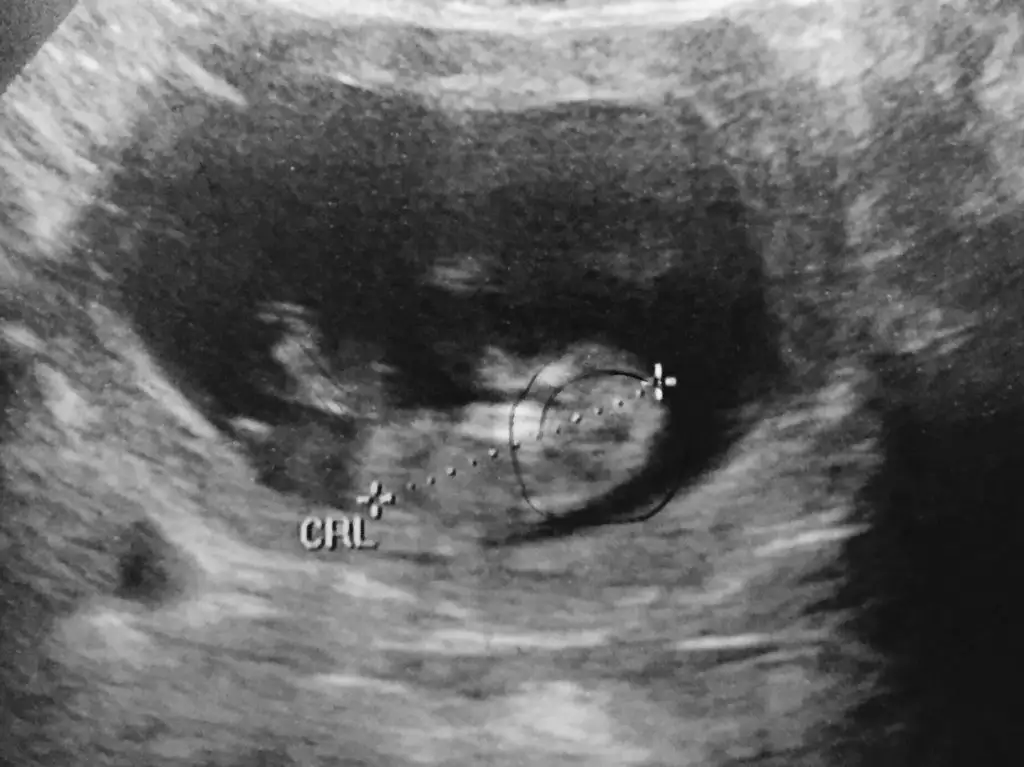

Canım şuan bir şey diyemiyorum çünkü çok küçük. Bu teori için en az 11 haftalık olması lazım. ikili teste gidersen o zamanki resmini koyarsan daha doğru bir şeyler söyleyebilirim.Herkese selam kızlar :) Tahminde bulanabilirmisiniz Eki Görüntüle 1492946

Bence nub. Ve erkek bu bebis galuba.. cunku kordon olsa daha yukarda olur .. kac haftalik ?Arkadaslar bakarmısınız bu çıkıntı Nub çıkıntısı mı eger öyleyse kız mı erkek mi?

Canim nub u paralel evet kiz olabilir..bizim ki bi tahmin..kesin olamaz..hayirli olsun canim bebeisinBaksana cnm bu Nub çıkıntısı mı eger öyleyse kız mı

Erkeğe daha çok benzettim ben canım. Yukarı doğru açılı duruyo.Arkadaslar bakarmısınız bu çıkıntı Nub çıkıntısı mı eger öyleyse kız mı erkek mi?